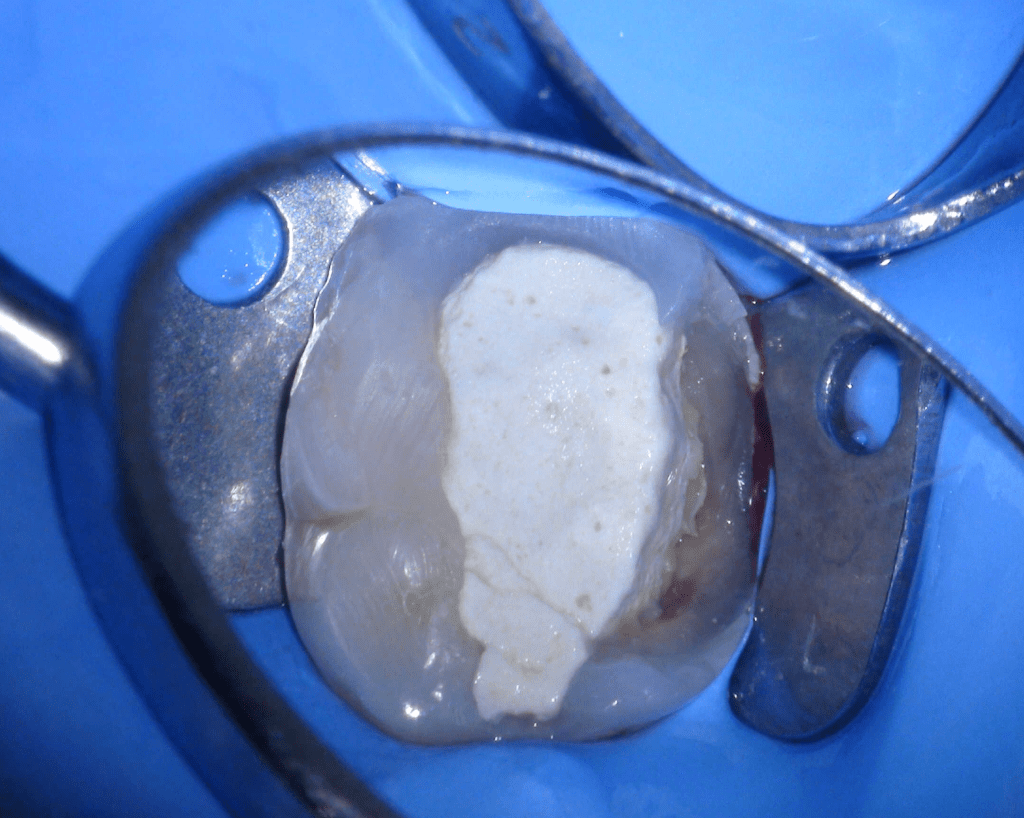

Pulpotomía biodentine + reco preendio